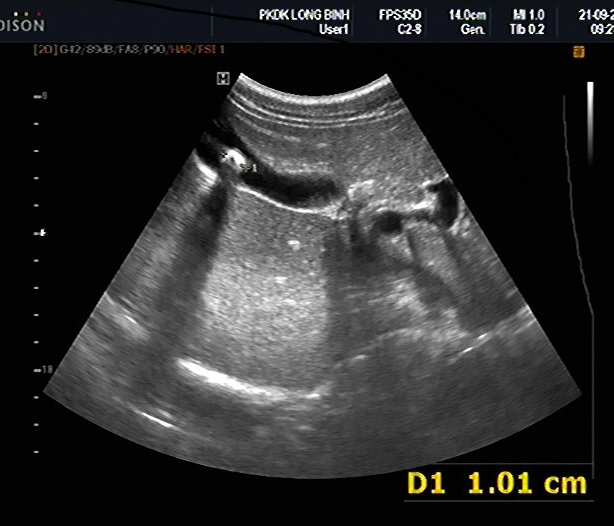

Calcul vesicule biliaire :

Image hyperechogene de 10mm en C forme

avec espace de

vide ascoustique posterieure en voyant tres fine .

Image echographique du foie |

Image echographique

hyperechogene de deux calculs de la vesicule

biliaire . Cone de l'ombre sont en vue tres net |

Image de hypoascoustique posterieure de

calcul est toujour en se presentee . Meme cas

en un autre plan de coupe |